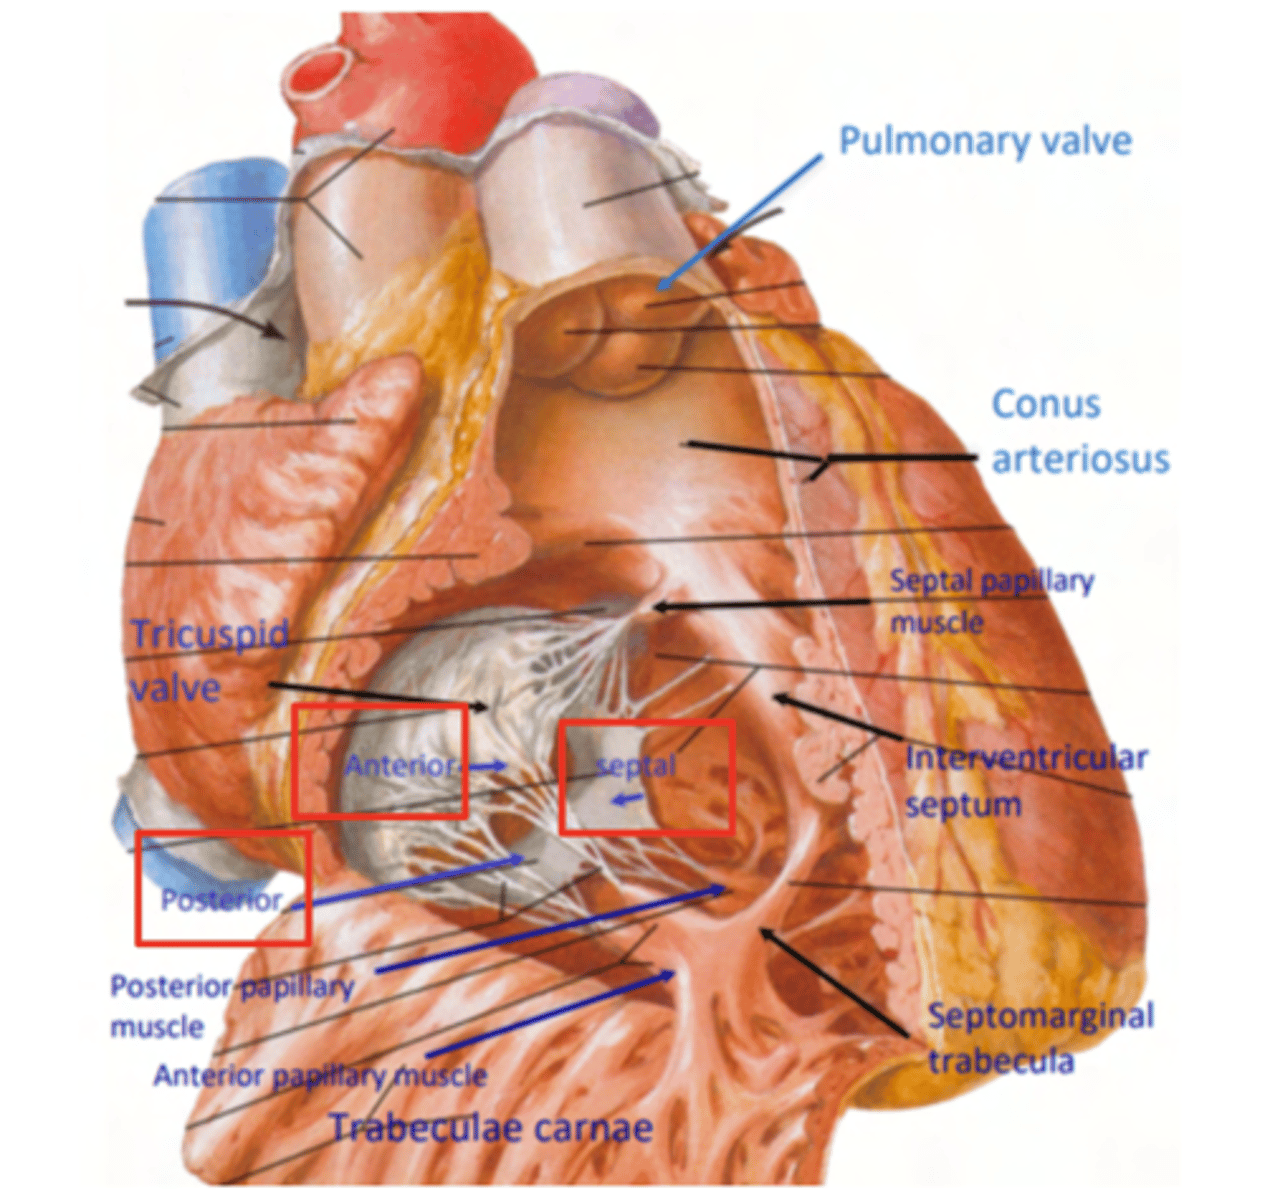

What are the walls of the right ventricle?

. Anterior wall

. Posterior wall

. Septal wall

Right ventricle has a conical shape with 2 o 3 walls

Describe the two portions of the medial/septal face/wall of the right ventricle.

infundibulum or outflow region or conus arteriosus (smooth and membranous)

trabeculae carnae (muscular and irregular)

What are the 3 cusps of the tricuspid valve?

Anterior

Posterior

Septal

What connect the cusps of the valve a to papillary muscles in the

right ventricle?

Chordae tendinae

With the contraction of the walls of the ventricle what's the action of the papillary muscles?

contract as well

With the contraction of papillary muscles what will be happen with the valve?

Close

What is the septomarginal trabeculae (or moderator band)?

Part of the conduction system of the heart.

electrical waves pass through this band to reach the papillary muscles.

LANDMARK